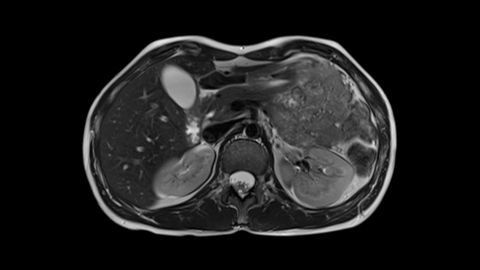

Magnetic resonance imaging (MRI) is a medical imaging technique used in radiology to form pictures of the anatomy and the physiological processes of the body in both health and disease. 3T MRI scanners use a magnetic field twice as strong as the traditional 1.5T. MRI also uses radio waves, and field gradients to generate images of the inside of the body.

MRI is widely used in hospitals and clinics for medical diagnosis, staging of disease and follow-up without exposing the body to ionizing radiation. 3T MRI brings additional sharpness to the images, helping determine borders and other details.

Whole Body MRI is an imaging technique that utilizes MRI scans of large areas of the body to acquire multiple structures within one scan. A total of 4 scans are required to include the entire body, from head to foot.